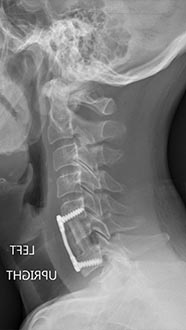

35 year old man presenting with severe neck pain with radiation down the right arm with right bicep weakness. MRI with large right C5-6 disc extrusion.

Postoperative xrays after C5-6 anterior cervical disc replacement. Complete resolution of arm pain and full painless range of motion of his neck.